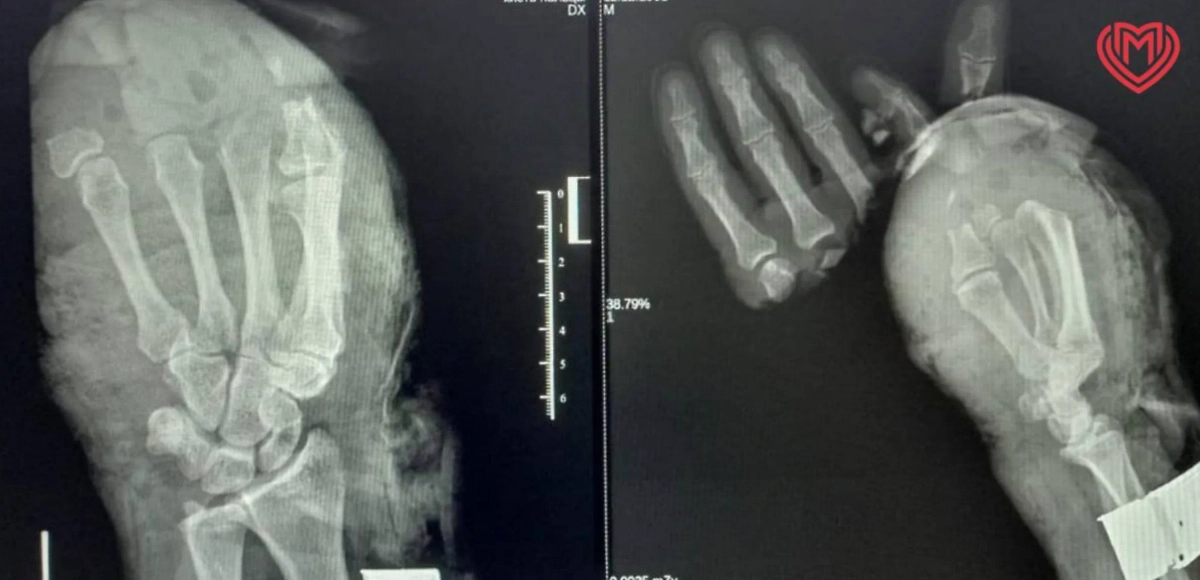

Рентген оторванных пальцев. Обложка © Telegram / Московская медицина

Врачи Центра микрохирургии кисти ГКБ имени А. К. Ерамишанцева впервые провели крайне сложную операцию, в ходе которой они пришили на место сразу пять пальцев, оторванных на производстве. Об этом сообщает пресс-служба департамента здравоохранения Москвы.

«В процессе операции был выполнен остеосинтез костей спицами, чтобы зафиксировать положение ампутированных пальцев, также были сшиты сухожилия сгибателей и разгибателей пальцев. На микрохирургическом этапе были сшиты вены и артерии, обеспечивающие приток и отток крови в пальцах и восстановлены пальцевые нервы для возвращения чувствительности в пальцах», — говорится в сообщении ведомства.

Сообщается, что это была первая операция, когда удалось пришить все пальцы во время одной операции. Врачи работали в две смены, а вся процедура заняла 14 часов. Известно, что все потерянные пальчики прижились успешно, и через неделю мужчина был выписан. Теперь его ждёт долгая реабилитация.